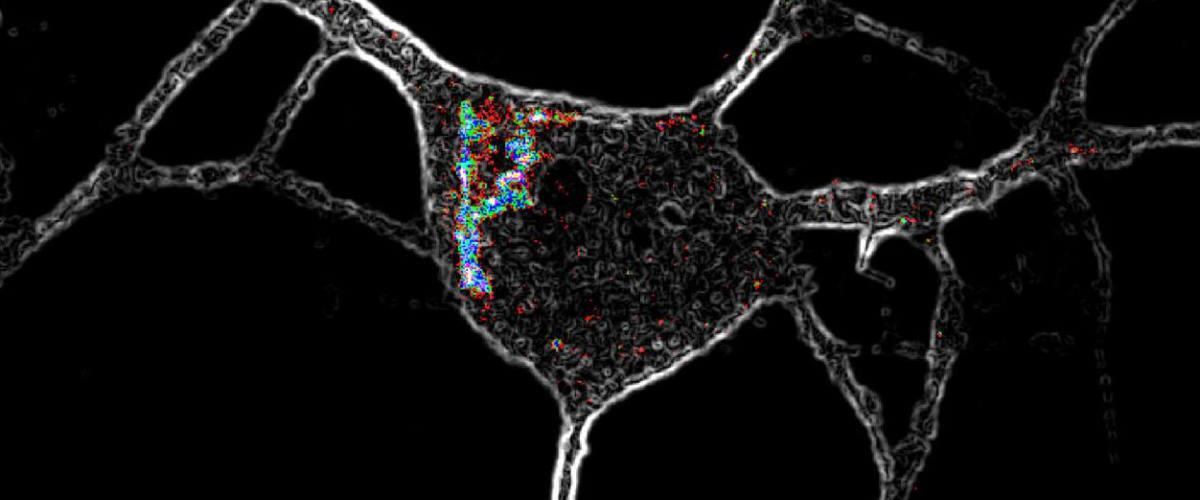

Чтобы выяснить, почему эти два типа химических веществ — психоделики и серотонин — по-разному влияют на нейроны, ученые модифицировали некоторые вещества, чтобы изменить то, насколько хорошо они активируют рецептор. Те вещества, которые были лучше подготовлены для активации 5-HT2A, все равно не заставляли нейроны расти. Вместо этого вещества, которые легко проходят через внешние жировые слои клеток, например, ЛСД приводили к разветвлению нейронов.

Серотонин имеет неравномерно распределенные электрические заряды и поэтому не может проникать в клетки и не вызывает их роста. Дальнейшие эксперименты показали, что большинство 5-HT2A-рецепторов корковых нейронов расположены внутри клетки, а не на поверхности, где ученые в основном их изучали.

Как только серотонин получил доступ к внутренней части корковых нейронов — через искусственно добавленные шлюзы на клеточной поверхности — он, как и ЛСД, вызвал рост клеток. На мышей вещество подействовало как антидепрессант. Через день после выброса серотонина животные, клетки мозга которых содержали неестественные точки входа, не сдавались так быстро, как нормальные мыши, когда их заставляли плавать.